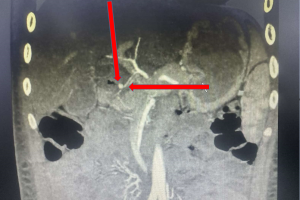

Cứu sống một trường hợp trẻ dị dạng bẩm sinh phế quản gốc bên phải xuất phát bất thường từ thực quản

Vừa qua Bệnh viện Nhi Đồng Thành Phố tiếp nhận trẻ Ng. Kh. H. 3 tháng tuổi, nữ, ngụ ở Bình Chánh, TP. Hồ Chí Minh. Khai thác bệnh sử trẻ bệnh 1 tuần, khởi phát...